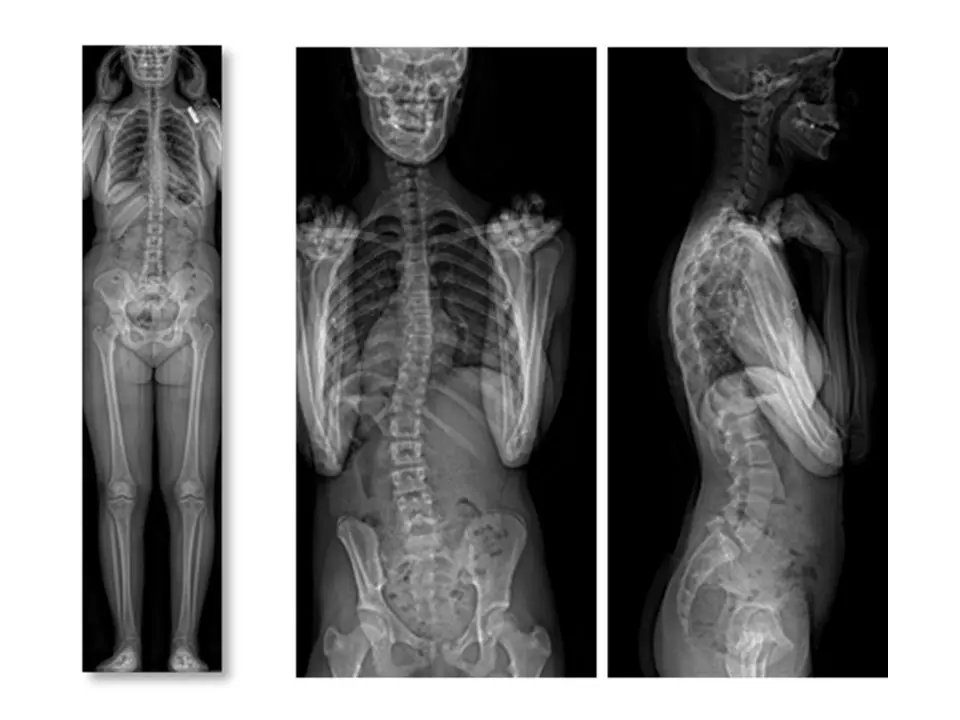

2023年7月から導入されたEOSedge イメージングシステム(EOS imaging社製)では、正面と側面の二方向から同時にX線を照射して撮影し、脊椎や股関節などの形体、配列の評価をおこなうことができます。

立ったまま(もしくは座ったまま)撮影するため、椎体や関節に体重がかかった状態で、全身の骨格を観察することができます。撮影データから3Dモデルを作成することで、脊椎や股関節の診断や手術の際に必要となる計測等が可能となります。